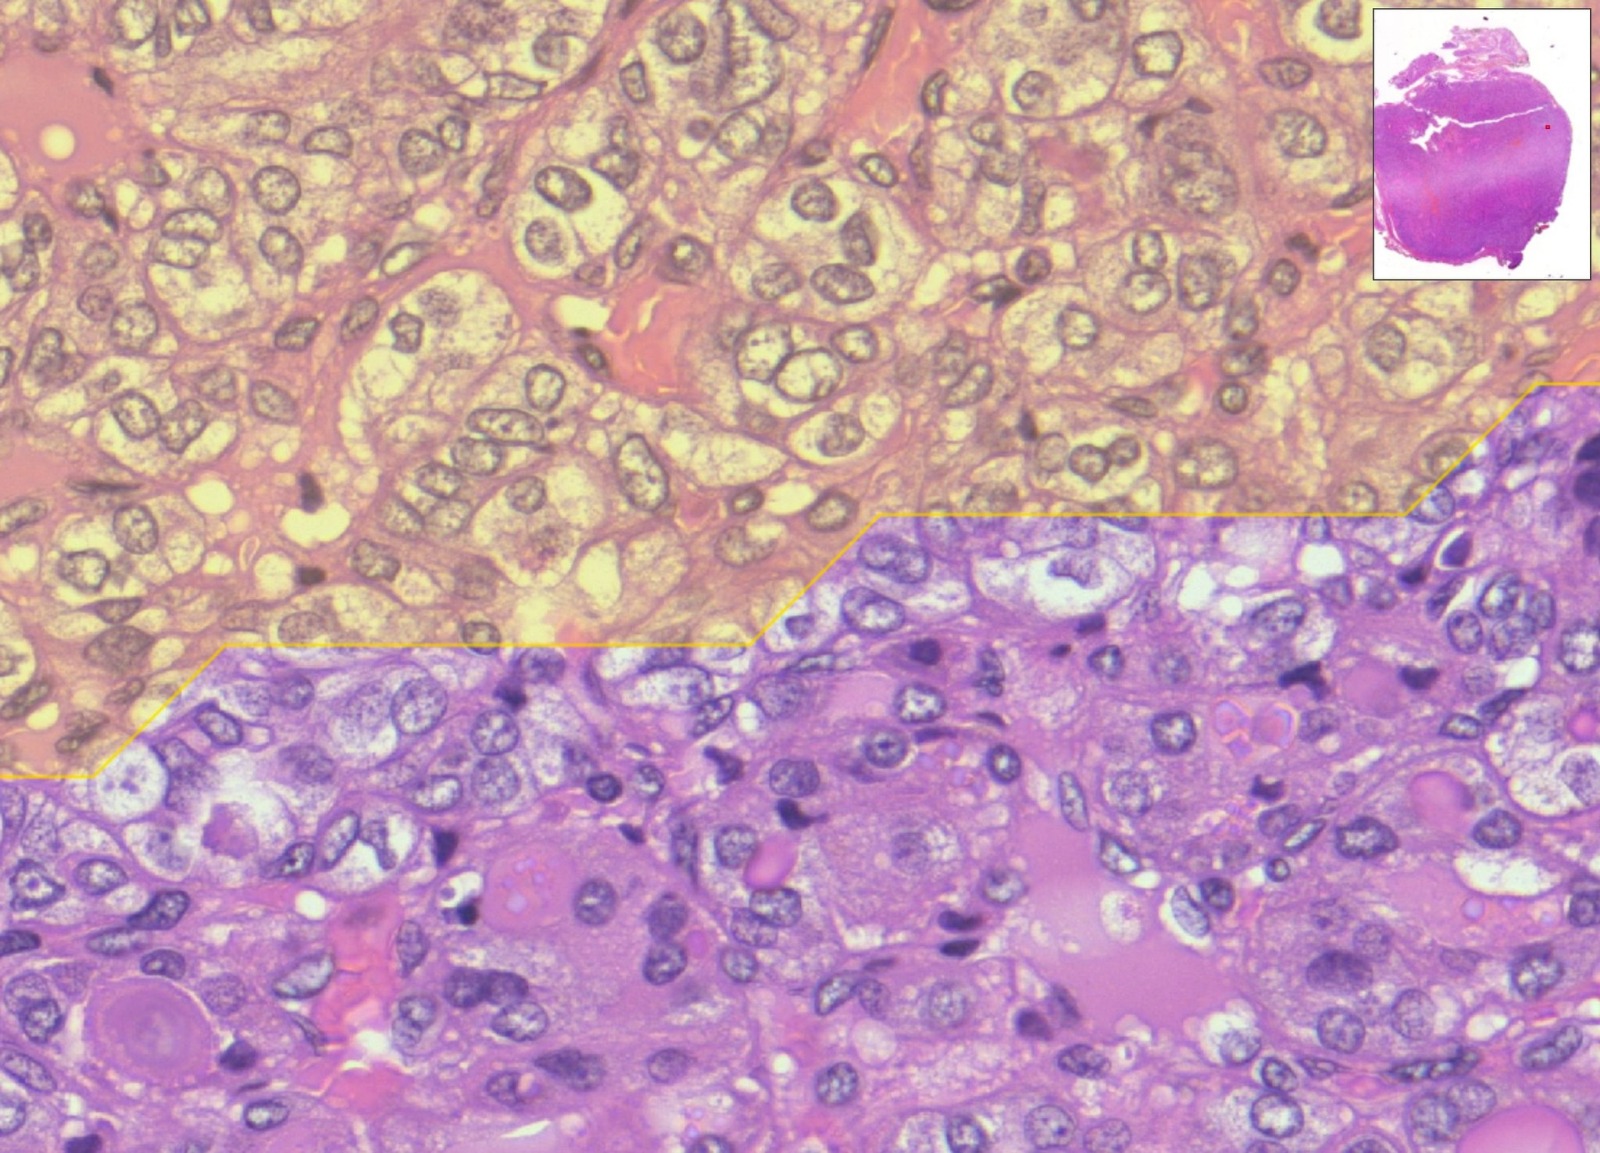

Si tratta di un algoritmo di digital pathology in grado di analizzare immagini istologiche ad altissima risoluzione in grado di fornire un aiuto significativo ai medici nella diagnosi di tumori. Il sistema utilizza reti neurali profonde (strumenti di deep learning, dunque basate sull’Intelligenza Artificiale) addestrate su migliaia di campioni digitalizzati con scanner molto potenti (l’immagine ricavata dai vetrini istologici su cui si trovano le cellule da analizzare) per identificare automaticamente aree, cellule, marcatori sospetti, spesso difficili da rilevare da parte dell’occhio umano.

L’Intelligenza Artificiale analizza l’immagine del campione e punta letteralmente il proprio sguardo in modo rapido sulle aree che meritano l’attenzione dei medici, velocizzando in tal modo la diagnosi e rendendola più efficace. Più nello specifico, il sistema sviluppato nella ricerca mette in campo un “doppio occhio”, due reti neurali che lavorano in sequenza: un primo “occhio digitale” coglie i dettagli delle cellule, un secondo “occhio” considera la visione d’insieme dell’immagine. Integrando le due letture, MiThyCA indica le aree che è opportuno analizzare per prime.